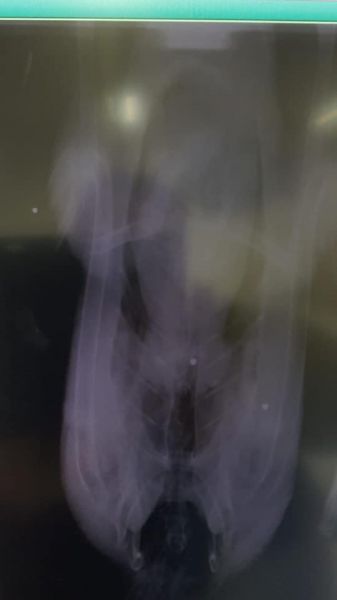

Eenmaal in het Natuurhulpcentrum aangekomen, werden beide dieren volledig onderzocht. We vonden uiterlijk geen symptomen of wonden. Maar toen we even later van beide dieren een röntgenfoto maakten, was alles ineens duidelijk: de dieren waren beschoten! Het lichaam van het overleden dier bevatte 3 hagelbolletjes; het levende dier draagt 1 bolletje in zich mee. Het hoeft niet gezegd dat dit een zwaar misdrijf is en dat deze zwanen beschermd zijn bij wet. We brachten het Agentschap Natuur en Bos op de hoogte die verder zal onderzoeken wat er precies gebeurd is in Arendonk. De levende zwaan wordt nu verder verzorgd en we duimen dat het goedkomt met dit prachtige dier.